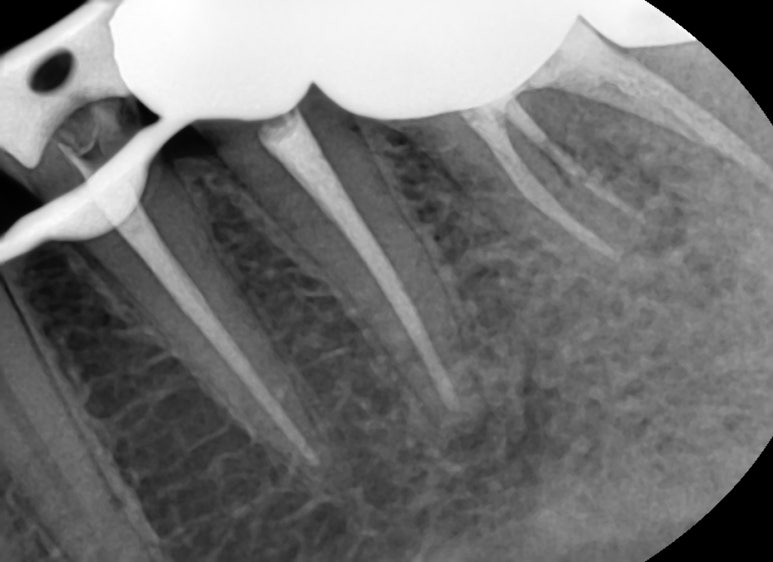

이런 치료과정을 거쳐 신경치료를 하였습니다.

결국 2019년에는 인레이 정도로 끝날 수 있었던 치료가

2021년에는 충치가 더 진행되고 치아가 깨져 신경치료와 크라운치료가 필요한 상태가 되어 신경치료와 크라운을 하게 되었죠.